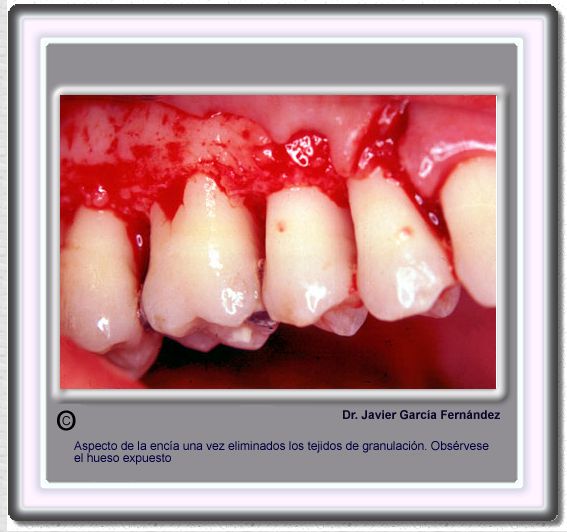

image 682